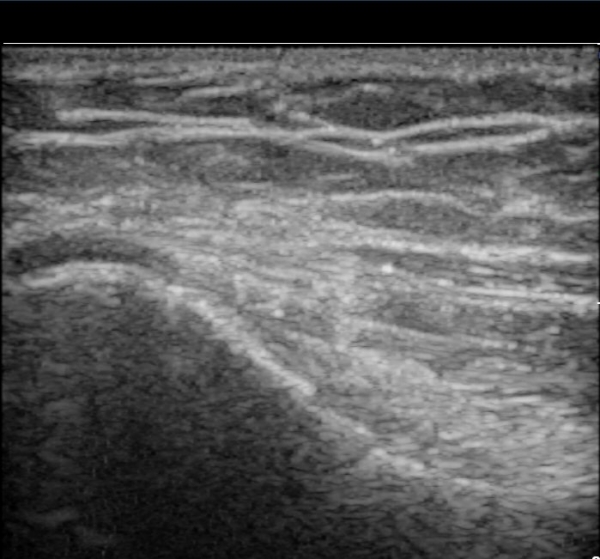

ÃÊÀ½ÆÄ °Ë»ç

³»»ó°ú Á¾´Ü¸é°Ë»ç¿¡¼­ ³»»ó°ú ±¼°ñ°Ç ºÎÂøºÎ¿¡ Àú¿¡ÄÚ º´º¯ÀÌ °üÂûµÈ´Ù. °Ç ½ÉºÎÀÇ

³»ÃøºÎÀδë´Â ƯÀÌ ¼Ò°ßÀ» º¸ÀÌÁö ¾Ê´Â´Ù(±×¸² 1, 2).

ŽÃËÀÚ¸¦ Á¶±Ý À̵¿ÇÏ´Ï °Ç ÀϺδ Á¤»óÀûÀÎ ¼Ò°ßÀ» º¸À̰í ÀÖ´Ù(±×¸² 3).